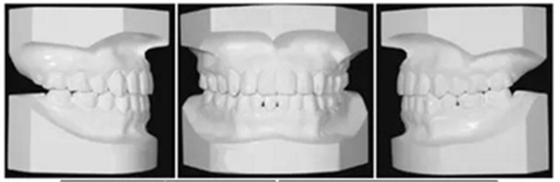

治療后面部和口內(nèi)照片顯示治療結(jié)果很成功(Figure 8)?;颊叩拿嫘瞳@得了非常顯著的改善,尤其是在唇部區(qū)域。覆合從-3.5mm增大到3.5mm,覆蓋從1.2mm增大到2.0mm。獲得了I類磨牙關(guān)系,沒有擁擠(Figures8 and 9)。

全景片顯示上前牙區(qū)未發(fā)生進(jìn)行性牙根吸收。然而,在下磨牙區(qū)有輕度牙根吸收,并且牙根平行性有改善空間(Figure 10A)。

頭測顯示:下頜平面角從46.7°減小到44.0°。上頜第一磨牙高度減小1.2mm。面高有減小(N-Me: 133.2 mm to 127.7 mm, Ans-Me: 78.5 mm to 72.6 mm; Table 1,Figures 10B and 11)。上下頜切牙顯示腭側(cè)和舌側(cè)傾斜(U1-SN: 95.8°to 91.8°, IMPA: 83.7°to 77.7°)。

治療前后頭影疊加圖清楚地顯示,下頜發(fā)生逆時針旋轉(zhuǎn),上下切牙舌側(cè)移動(Figure 11)。CT顯示髁突未發(fā)生形態(tài)改變,而磁共振T2影像顯示有形態(tài)改善(未提供圖像)。在治療期間沒有出現(xiàn)顳下頜關(guān)節(jié)癥狀。